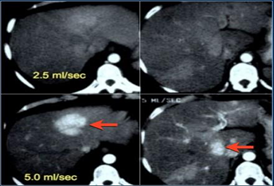

Những năm vừa qua được sự quan tâm của thủ trưởng các cấp cùng với sự đầu tư của Đảng ủy, Ban giám đốc Bệnh viện trong chẩn đoán và điều trị, bệnh viện đã trang bị nhiều máy móc hiện đại, trong đó đặc biệt có máy CT Scanner 16 Slice SIEMENS của Cộng Hòa Liên Bang Đức, cùng với sự chuyển giao kỹ thuật, công nghệ mới, các bác sỹ và kỹ thuật viên đã làm chủ hoàn toàn các kỹ thuật phức tạp mà chỉ có tuyến tỉnh và trung ương mới đáp ứng được như: Chụp CTscanner có thuốc cản quang gan ba thì, ổ bụng, lồng ngực, sọ não, hệ mạch máu bụng, chậu, chi…Trong thu dung cấp cứu, máy CT Scanner càng phát huy thế mạnh trong chẩn đoán chấn thương sọ não, chấn thương bụng kín…